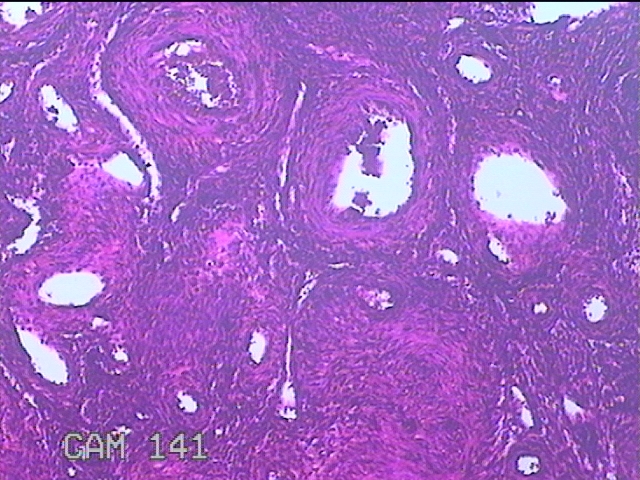

宫腔切除组织

性别

女

年龄

46岁

临床诊断

子宫内膜息肉

一般病史

月经淋漓不净7月,发现宫腔赘生物14天。

标本名称

大体所见

灰白暗红色不规则肿物2.7x2x0.8cm一个,表面糜烂,切面肿物呈实性,切面灰白粉红色,质软。